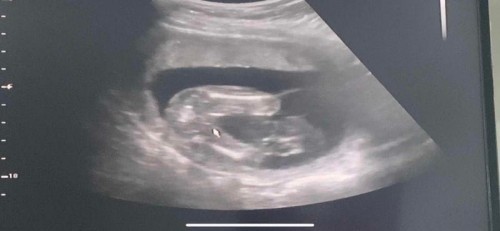

คุณหมอบอก น้องไม่มีหัวเต่าค่ะ 18W ❤️👧🏻

ไปอัลตราซาวด์เมื่อวาน น้องเอาขาหนีบไว้ เลยต้องรอลุ้นอย่างเดียวเลยค่ะ บ้านนี้